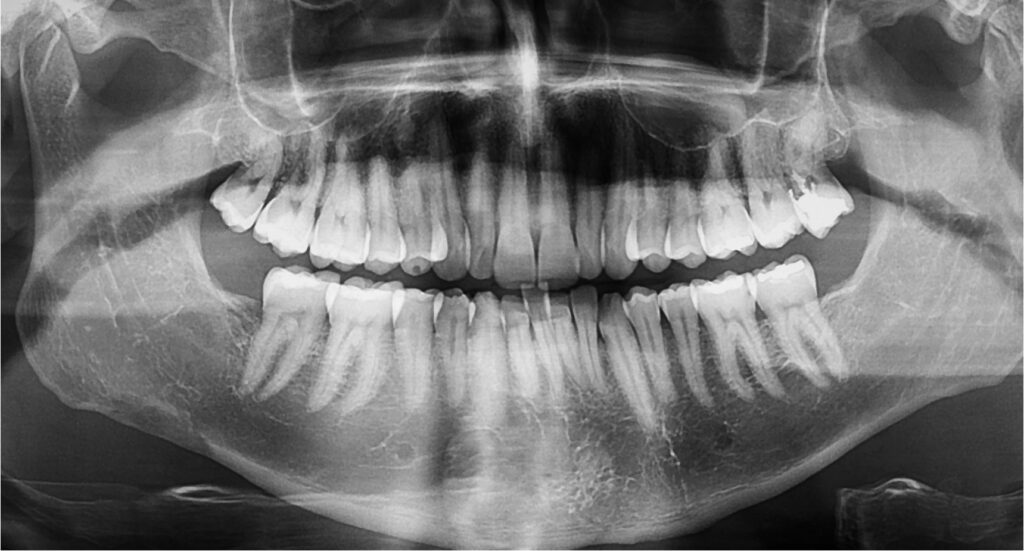

実際、レントゲンでよく見ないと分からない程度の吸収がほとんどで、患者さん自身が自覚することはほぼありません。

多くの場合、治療前のレントゲン検査で

- もともと歯根が短い歯

- 過去の外傷が疑われる歯

をある程度把握することができます。